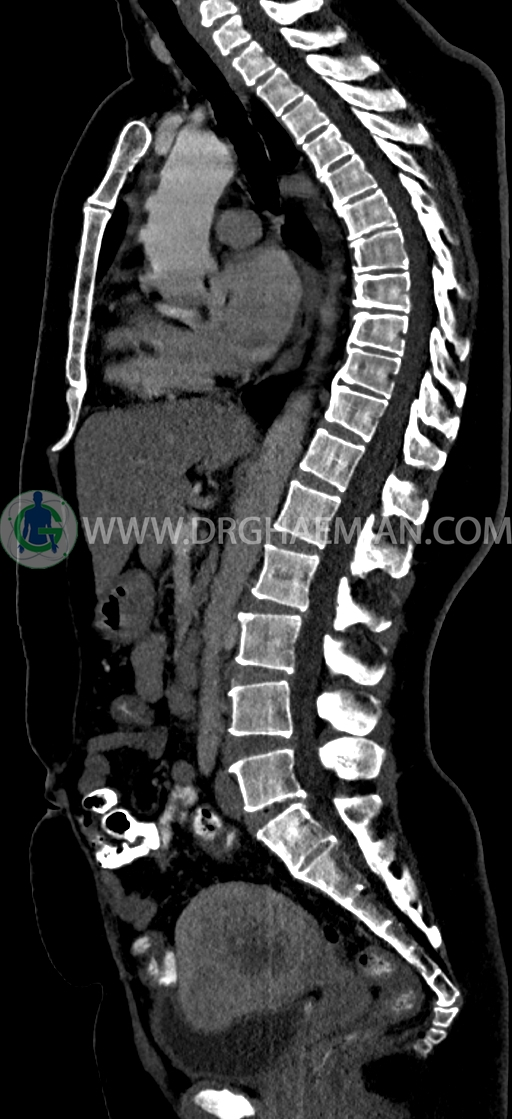

در سي تي اسکن اسپيرال ريه و مدياستن-شکم و لگن با کنتراست خوراکی و وريدی (مولتي ديدکتور 16 با مقاطع ظريف و بازسازي هاي ساژيتال و کرونال) :

–Bridging osteophyte در مهره هاي توراسيک مطرح کننده DISH همراه با کيفوز مشهود است.

–lumbosacral transitional vertebrae